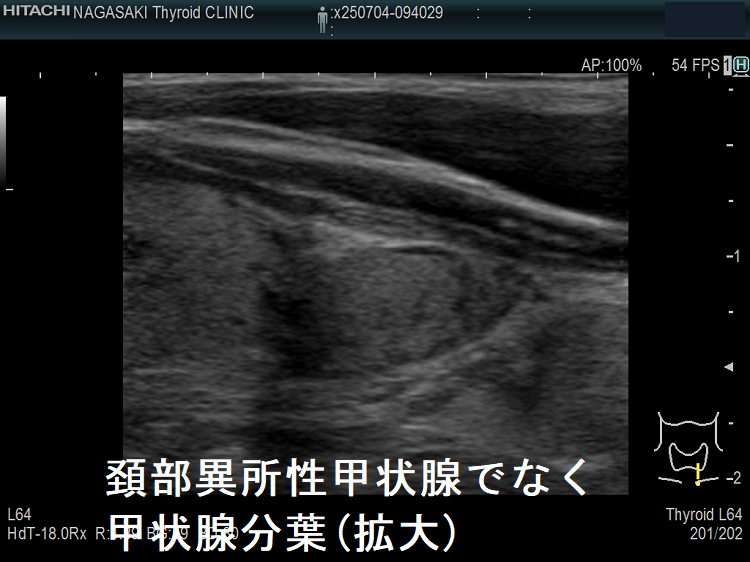

頚部異所性甲状腺でなく甲状腺分葉

頚部異所性甲状腺のように見えても、微妙に甲状腺本体と連続していて甲状腺分葉の場合があります。

頚部異所性甲状腺でなく甲状腺分葉(拡大)

頚部異所性甲状腺でなく甲状腺分葉 超音波(エコー)画像 矢状断 (拡大)